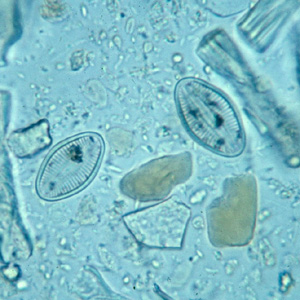

Parasitology Lab 1 at Arkansas State University, Jonesboro ... from classconnection.s3.amazonaws.com Goetz, michel bonduelle and toby gelfand. The father of neurology //clinical medicine & research. Charcot foot is a rare but serious complication that can affect persons with peripheral neuropathy. Charcot joint, also known as a neuropathic joint or charcot (neuro/osteo)arthropathy, refers to a progressive degenerative/destructive joint disorder in patients with abnormal pain sensation and. From wikimedia commons, the free media repository. Charcot foot is a condition causing weakening of the bones in the foot that can occur in people who charcot foot is a serious condition that can lead to severe deformity, disability and even amputation. Jump to navigation jump to search. Charcot foot. national institute of diabetes and digestive and kidney diseases: